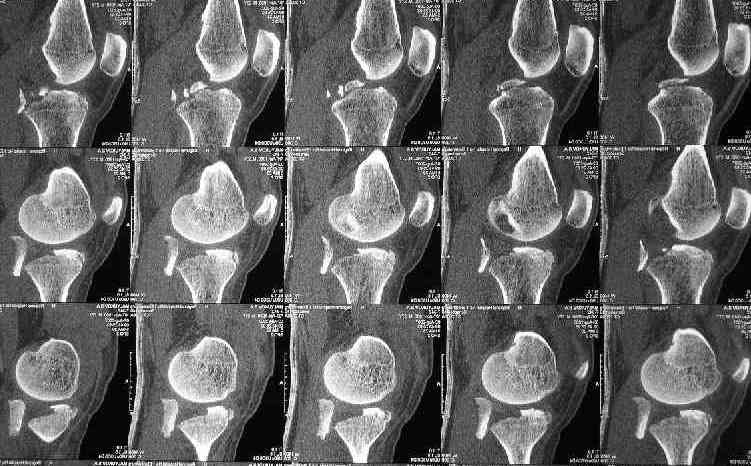

Для определения доступа сагитальные срезы менее информативны, необходимо иметь корональные срезы.

Корональные срезы дают информацию об апексе перелома, и также информацию о вовлечения суставной поверхности, что является немаловажным для прогноза.

Для фиксации переломов тибиал плато обычно применеяется техника создания buttress, пластинами с угловой стабильностью, но в данном случае эпифизарный фрагмент очень тонкий на всем протяжении и фиксировать такой перелом невозможно обычными традиционными методами фиксации.

Для лечения таких эпифизарных переломов применяется техника "создания исскуственного края тибиал плато".

Изгибаясь по контуру медиального эпифиза полу-или 1/3 тубулярные пластины создают медиальный край большеберцовой кости.

Радиально проведенные, через пластину и в эпихондральной зоне (пластина действует как шайба) тонкие 2.7 или 3.5 мм кортикальные шурупы до латерального кортекса создают адекватную фиксацию.

Мне кажется в данный момент нет необходимости гоняться за повреждениями связок. После решения проблем костей, при необходимости вторичная операция по восстановлению связочного аппарата. А с фиксацией кости необходимо торопиться, иначе, сростаясь, усложнит процесс восстановления.